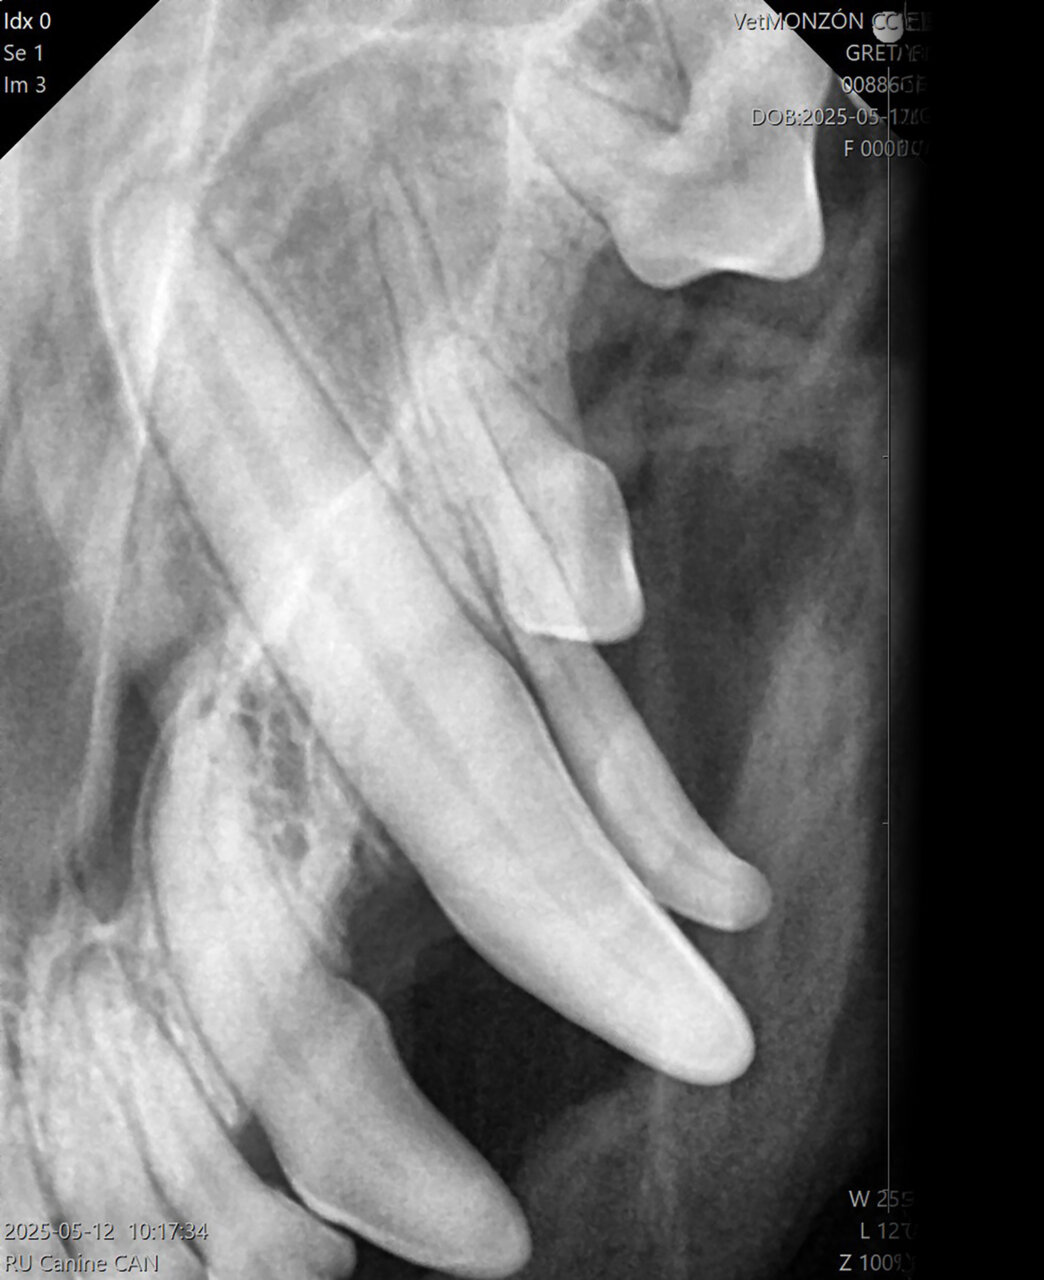

En función de la relación diente/sensor podremos utilizar dos técnicas radiográficas diferentes:

- Técnica paralela: el captador se coloca paralelo al diente y el haz de rayos X se proyecta perpendicular al mismo (imagen 3). Esta colocación solo puede llevarse a cabo con los dientes premolares y molares de la mandíbula.

- Técnica en bisectriz: para evaluar el resto de los dientes. El captador se coloca lo más paralelo posible a la raíz del diente y, a continuación, se halla el ángulo entre la raíz del diente y el captador. Este ángulo se corta por la mitad (bisectriz) y el haz de rayos se dirige perpendicular a esta (imagen 4).